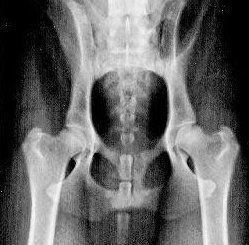

Vergelijk deze foto's eens en u kunt zeer waarschijnlijk zelf ook het verschil zien:

Op foto 1 ziet u hoe goede heupen horen te zijn. Op deze foto is duidelijk zichtbaar dat het hier goede heupen betreft: de kop sluit netjes in de kom, en de kom is regelmatig van vorm en mooi glad.